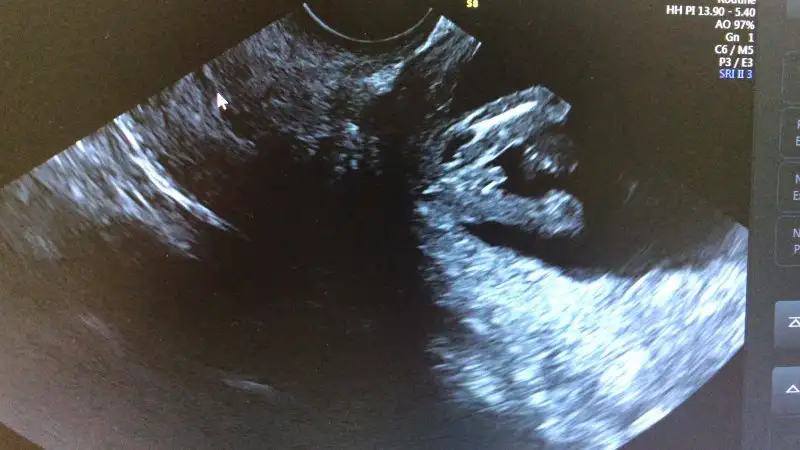

Benim bugün ki kesem de kız gibi geldi ama hissettiğim erkek :)

Ben ben keseyi gördüm ne bebeğiKızlar meraba bugün doktordan geldik

Herşey iyi çok şükür

Cinsiyet içinde tahmin yaptı ama bu haftada tam belli olmaz dedi

Birde dün ilk defa plesentayı gösterdi doktorum. Çok ilginç geldi. Göbek bağını bile gördüm:) kese ye baya yakınmış plesenta. Ama ileriki haftalarda yukarı çıkar dedi. Yoksa kanama yapabilirmiş. Ama %90 çıkacak dedi.